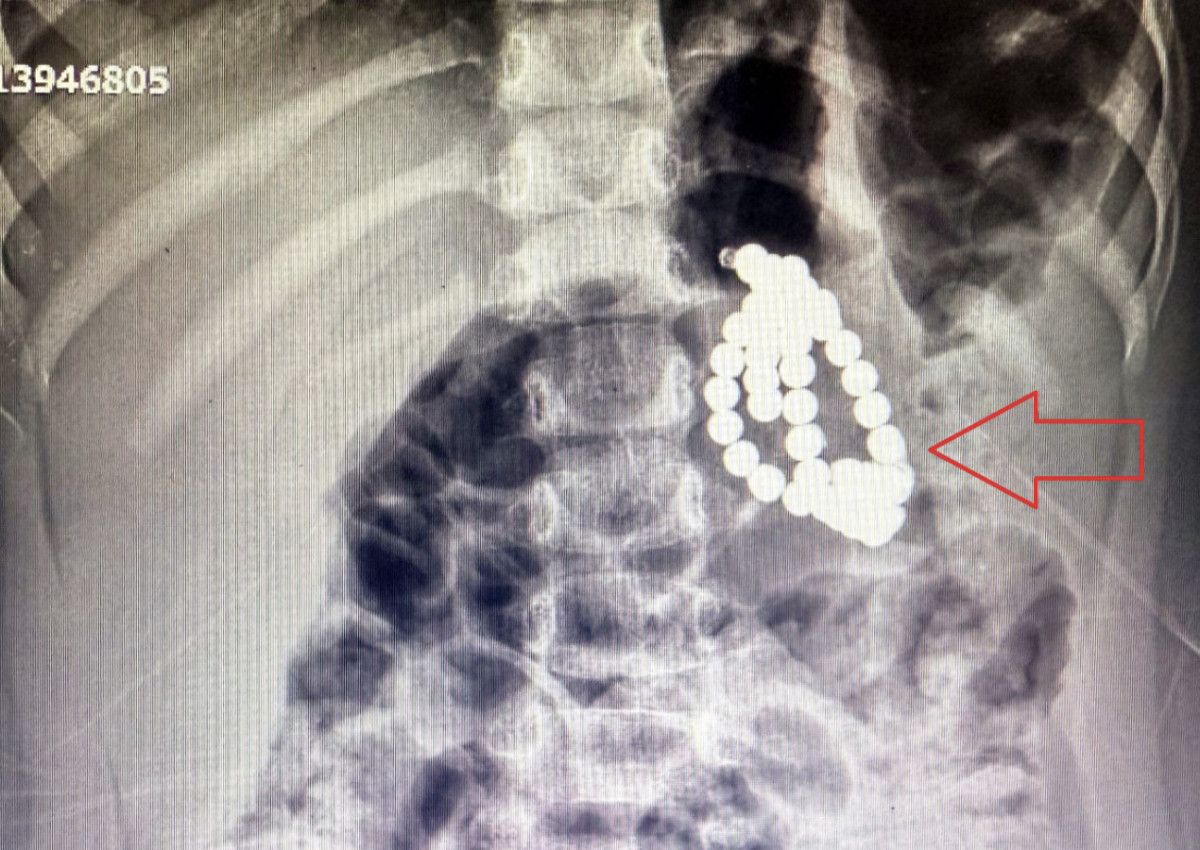

Çekilen röntgende, mide ve bağırsaklarında boncuk benzeri yabancı cisimler tespit edildi.

Aile kızlarının kolye ya da bileklik yuttuğunu düşünürken, doktorlar manyetik boncuklardan şüphelendi.

3 yaşında bir kız çocuğu. Acile mide bulantısı kusma şikayetiyle başvurdu. Röntgende, karında çok sayıda boncuğa benzer yabancı cisme rastlandı. Aile daha çok boncuk, bileklik tarzı plastik birşey yuttuğunu düşünüyordu. Görüntüye baktığımızda, son zamanlarda çok sık rastladığımız magnet boncuk yutma vakalarına benziyordu.

Fakat çoklu mıknatıs yutma, acil bir vakadır. Çünkü midede, bağırsaklarda yapışıklıklara ve delinmelere sebep olabilecek potansiyele sahiptir. Bir program vasıtasıyla bunun manyetik bir cisim olduğunu fark ettik ve hastayı ameliyata aldık.